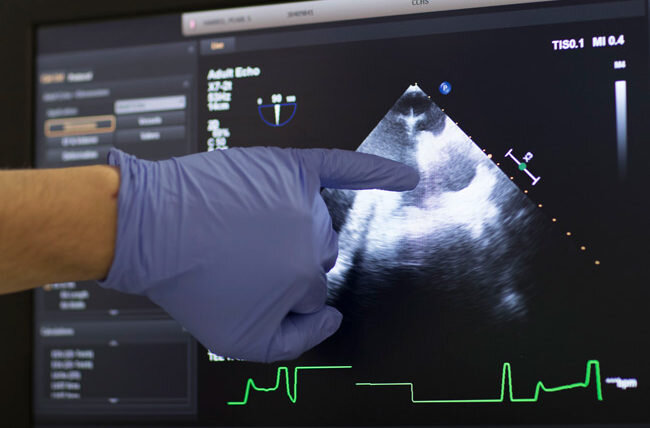

Предположим, к врачу обращается пациент с жалобами на периодическое повышение давления, при этом ранее никаких заболеваний со стороны сердца не было. Доктор, чтобы подтвердить диагноз артериальная гипертензия (или опровергнуть его) отправляет пациента на ЭКГ и на УЗИ сердца (ЭхоКС). На электрокардиограмме заключение: признаки гипертрофии левого желудочка; на ЭхоКС – гипертрофия левого желудочка, и/или гипертрофия МЖП (межжелудочковой перегородки). Теперь доктору понятно, что перед ним пациент с настоящей злостной гипертонией, ведь сердце уже изменило свою структуру и функцию и подстроилось под влияние повышенного давления.

Сердце состоит из двух предсердий и двух желудочков. Гипертрофия левого желудочка – это утолщение стенок главного сократительного отдела сердца; именно левый желудочек выполняет огромную работу: из него кровь под высоким давлением поступает в аорту, а затем и в большой круг кровообращения, чтобы обеспечить кислородом все органы.

Сердце находится в режиме постоянной повышенной нагрузки, наступает момент, когда оно теряет свою эластичность и способность расслабляться. Затем развивается так называемая диастолическая сердечная недостаточность: из-за того, что сердце плохо расслабляется, в его камеры поступает критически малый объём крови, которого недостаточно для кровоснабжения всего организма (камеры становятся маленькими - это видно на изображении выше). И тут начинается порочный круг, из которого очень тяжело выбраться, ведь изменения в сердце уже необратимы!